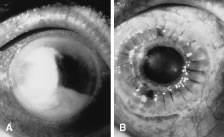

Candida infection typically produces epithelial ulceration, focal necrotizing stromal inflammation, moderate cellular infiltrate and edema in the adjacent stroma, and mild or moderate iritis in the early stages, indistinguishable from bacterial keratitis (Figs. 15, 16, and 17). Fungal elements cannot be detected by biomicroscopy. If untreated, the keratitis evolves to produce dense suppuration and necrosis of the deep stroma. Although multifocal suppuration may develop in polymicrobial keratitis, there is no distinctive sign of mixed Candida and bacterial infection (Fig. 18).